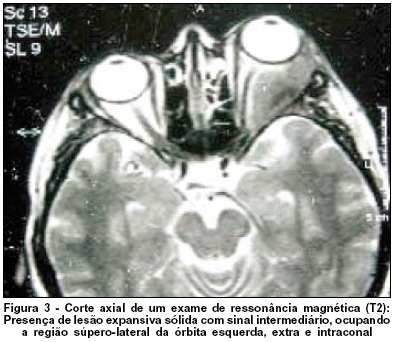

O exame clínico sistêmico não apresentou alterações, assim como os testes de função tireoidiana (T4, TSH). O exame de tomografia computadorizada de órbita (Figura 2) apresentava uma lesão intra e extraconal com densidade de partes moles hiperdensa com realce após contraste. A imagem por ressonância magnética de órbita apresentava uma lesão expansiva sólida com sinal intermediário em T1 e T2 (Figura 3) que ocupava a região súpero-lateral da órbita esquerda, extra e intraconal, deslocando medialmente a musculatura extrínseca adjacente e o nervo óptico esquerdo, determinando acentuada proptose. Houve realce após injeção endovenosa do contraste paramagnético (gadolíneo). Não havia definição da glândula lacrimal esquerda, que permitisse observar plano de clivagem com a lesão.